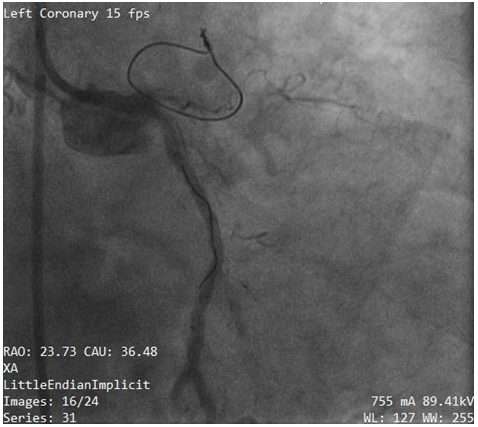

Subsequently, we made several attempts using simple manoeuvers like traction, pull and push without success. Unfortunately the guide wire was fractured and entrapped leaving part in LCX and LM (Figure 2). The patient suddenly complained of severe chest pain. The blood pressure went down to 70/50mmHg. The fluoroscopic test injection show severe LM (Figure 3) and left circumflex (LCX) artery dissection (Figure 4). Due to rapid hemodynamic destabilization, Subsequently, LM stenting with 3.5x18mm Biomatrix Alpha drug eluting stent (Biosensors, Shangdong, China) was performed (Figure 5). Another Biomatrix Alpha (Biosensors, Shangdong, China) drug eluting stent (DES) 2.75×18mm was successfully crossed with the broken guidewire and was deployed at LCX to sealed the fractured fragment to the vessel wall.The procedure result was excellent with Thrombolysis in Myocardial Infarction (TIMI) 3 flow distally (Figure 6). After the placement of the stents, an intra aortic balloon pump (IABP) was placed. The patient’s chest pain was resolved. The hemodynamic condition was improved but we later observed retained filaments in the ascending aorta (Figure 7 & 8). The patient declined surgical intervention for removal of these stray filaments and was discharged the following day with stable condition. During the subsequent monthly follow up visits, she was in a good condition and follow up with triple anti-platelet medication with no complications.

Figure 3 Angiography confirmed the left main (LM) dissection.

Figure 4 Angiography confirmed the left circumflex artery (LCX) dissection.